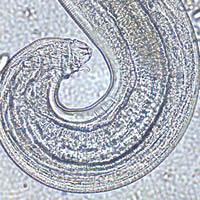

A family from Afghanistan immigrated to the United States to live in Missouri.

Stool specimens were collected from all family members and submitted to

the Missouri State Health Laboratory for an O & P (ova and parasites) examination.

The specimens were divided into vials containing 10% formalin and PVA. Smears were made from the PVA preserved specimens, stained

with trichrome stain, and examined. The 10% formalin-preserved specimens

were concentrated using the FEA (formalin-ethyl acetate) concentration

method. Wet mounts of the sediment were examined. Some of the

organisms identified in the stool specimens from family members included

Giardia intestinalis (lamblia) cysts, Endolimax nana

cysts and trophozoites, Hymenolepis nana eggs, and Entamoeba

hartmanni cysts and trophozoites. A worm-like object was discovered

in the stool concentrate from a 5-year-old family member. Figures

A, B, and C are detailed images of the object.

What is your diagnosis? Based on what criteria?